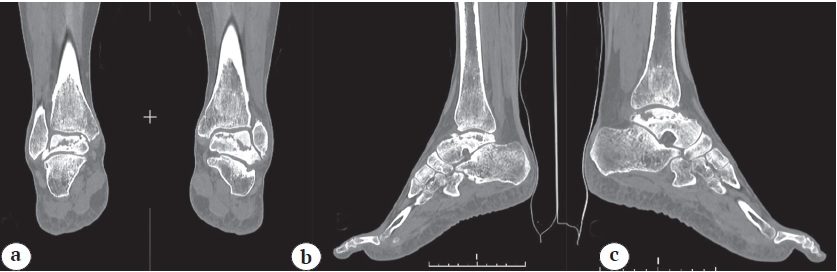

На контрольных рентгенограммах осевые соотношения в голеностопных суставах правильные, суставные щели равномерные, костных деструкций не определяется (рис. 4). Величина угла наклона пяточной кости левой стопы — 23°, правой стопы — 22°. Величина угла Maery левой стопы — 13°, правой стопы — 18°.

Рис. 4. Рентгенограммы обеих стоп и голеностопных суставов в послеоперационном периоде — суставные щели равномерные, костных деструкций не определяется: a — правая и левая стопы в переднезадней проекции через 8 мес. после последней операции; b — правая стопа в боковой проекции через 12 мес. после операции; c — левая стопа в боковой проекции через 8 мес. после операции

Figure 4. X-rays of both feet and ankles in the postoperative period; the joint gaps are equal, bone destructions are not observed: a — right and left feet in AP view in 8 months after the last operation; b — right foot in lateral view in 12 months after operation; c — left foot in lateral view in 8 months after operation